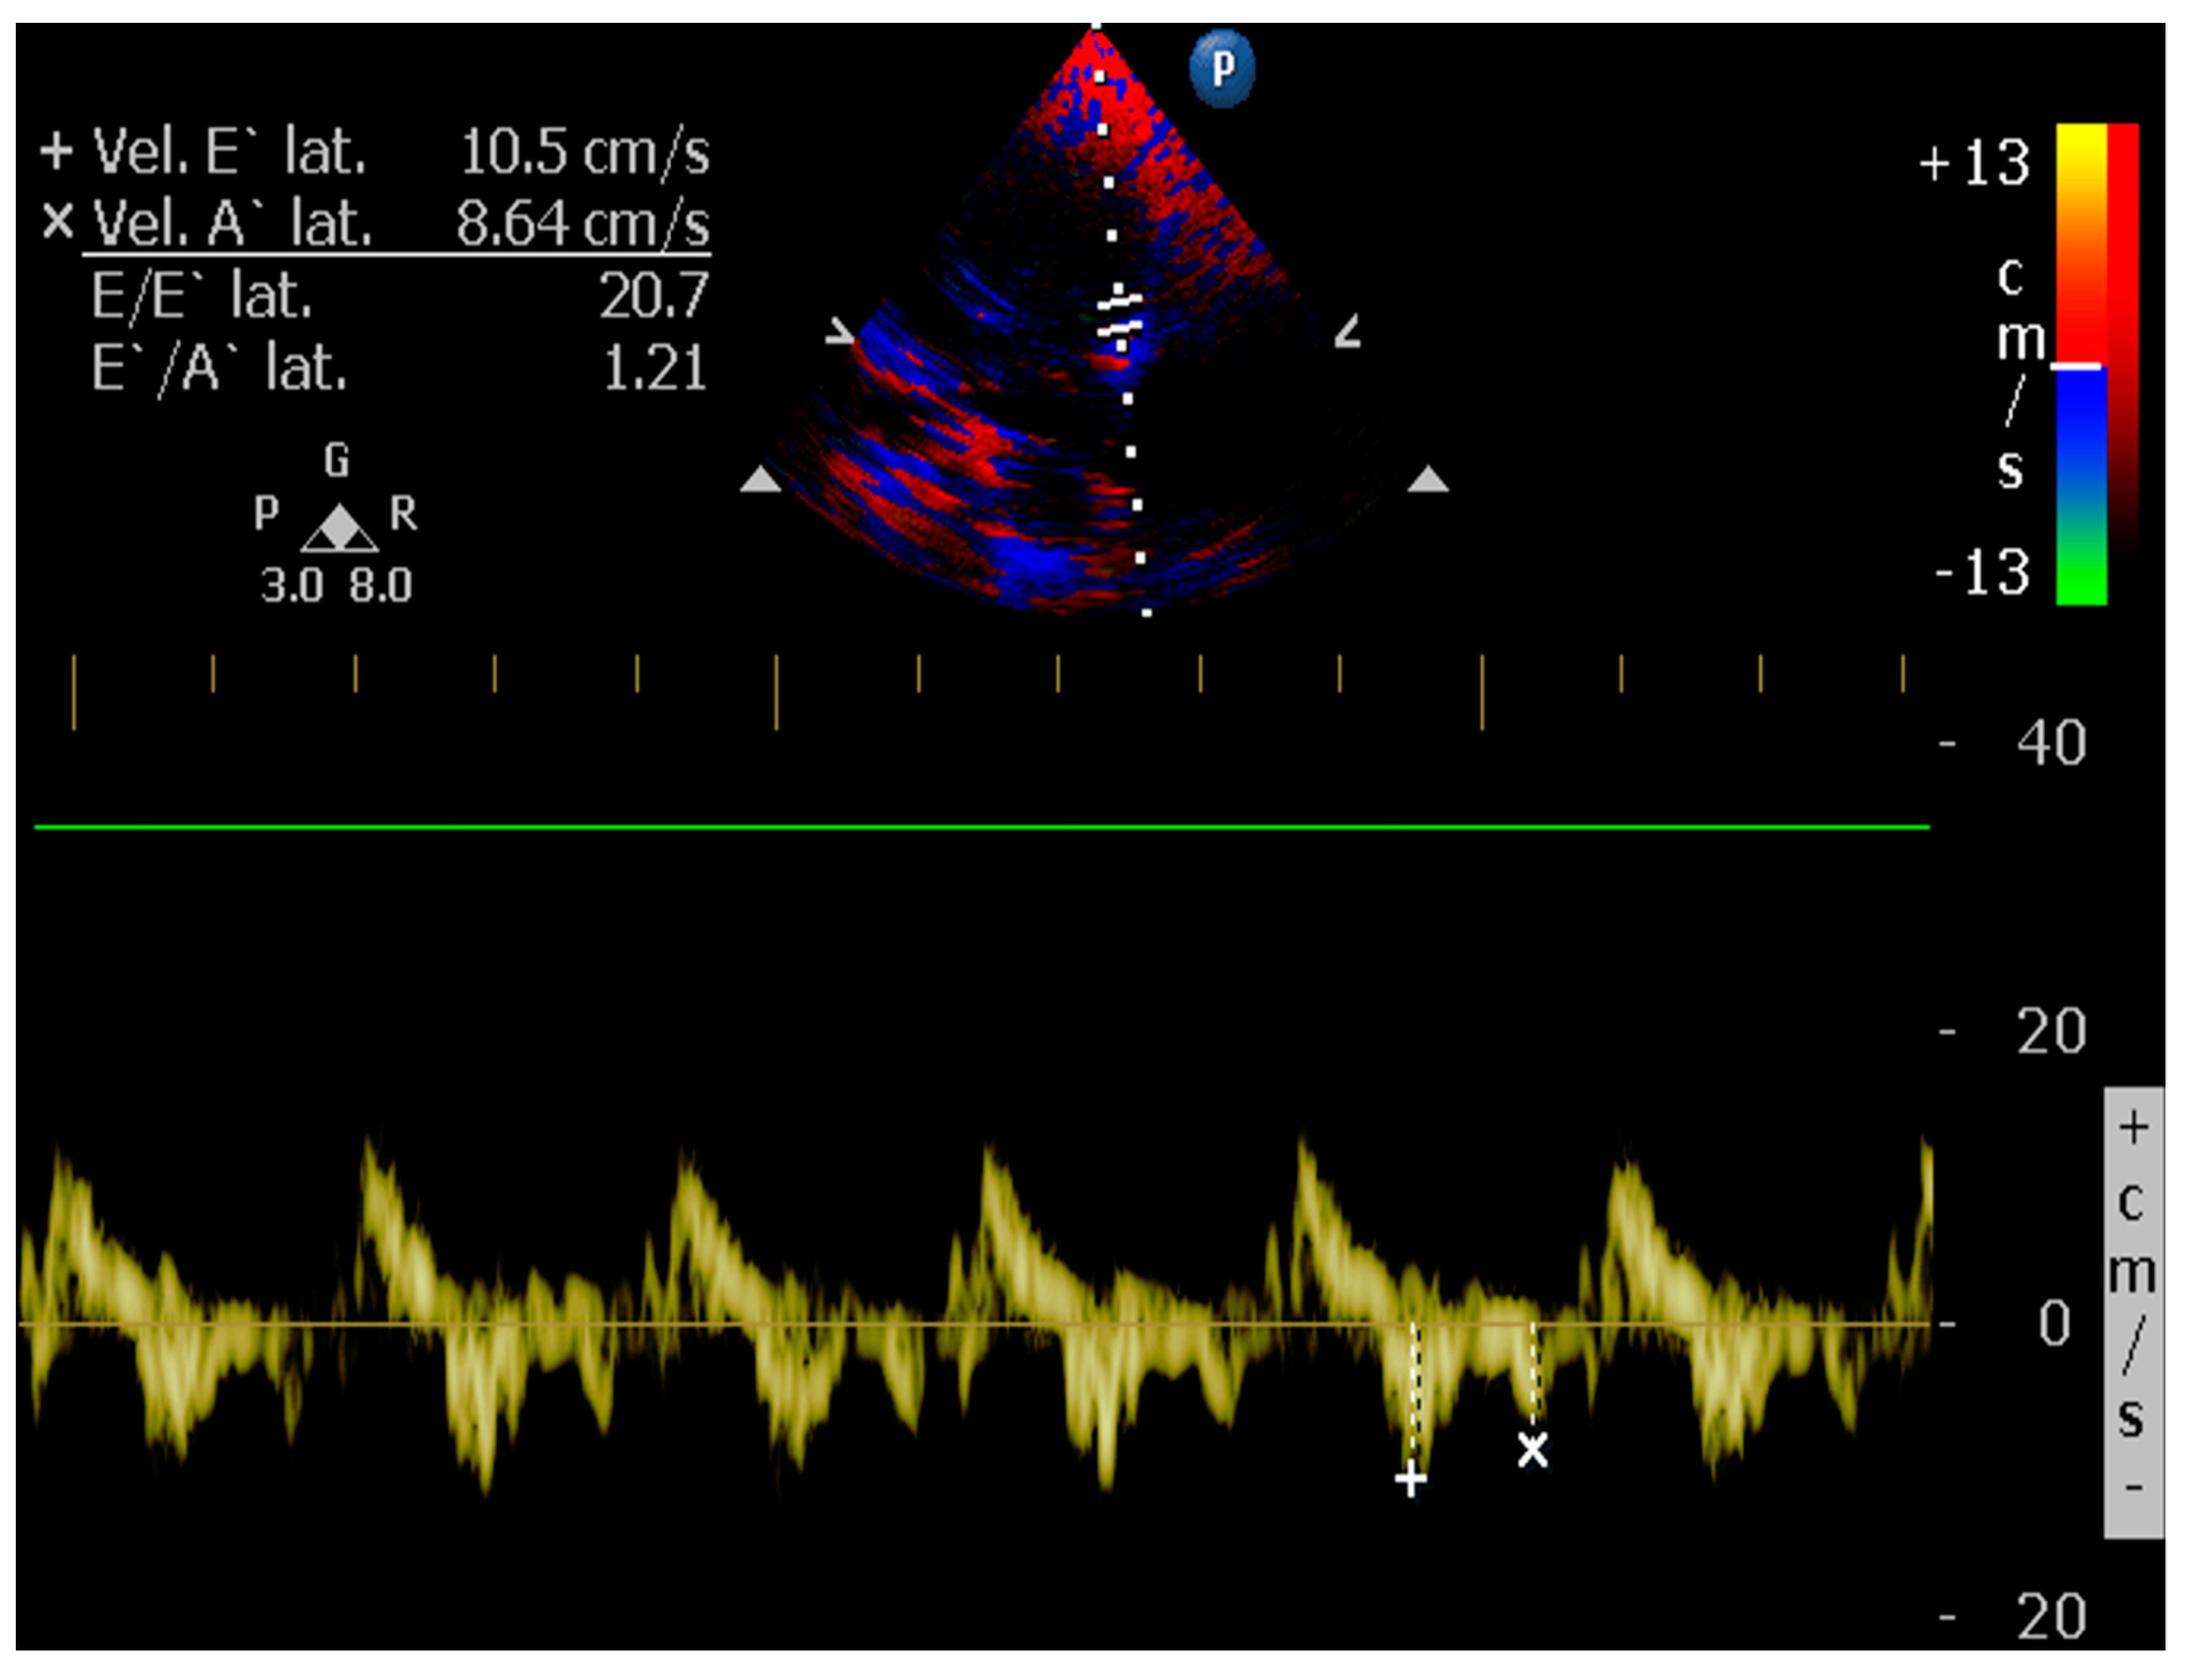

4.8.8. E/é Ratio of the Mitral Annulus

5.1.4. Tissue Doppler and Speckle Tracking

- Kim, J.H.; Park, H.M. Usefulness of conventional and tissue Doppler echocardiography to predict congestive heart failure in dogs with myxomatous mitral valve disease. J. Vet. Intern. Med. 2015, 29, 132–140. [Google Scholar] [CrossRef] [PubMed] [Green Version]

- Santos, M.; Rivero, J.; McCullough, S.D.; West, E.; Opotowsky, A.R.; Waxman, A.B.; Systrom, D.M.; Shah, A.M. E/e’ Ratio in Patients with Unexplained Dyspnea: Lack of Accuracy in Estimating Left Ventricular Filling Pressure. Circ. Heart Fail. 2015, 8, 749–756. [Google Scholar] [CrossRef] [Green Version]